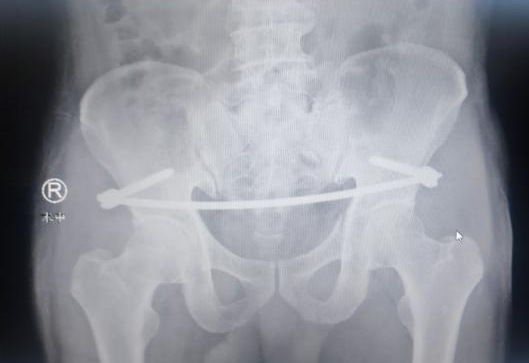

次日,任海东、信远、吴学业手术团队为患者进行了“骨盆复位内固定术”。在天玑骨科机器人的辅助下,置入INFIX螺钉,连接弯棒透视双斜位见骨折及双侧髂骨正位,调整复位骨盆前环骨折处,再次透视见骨折复位及固定满意。手术切口仅3公分,予以全层缝合,手术顺利。

术中